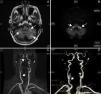

Afectación vascular del sistema nervioso central en la arteritis de células gigantes: una forma de presentación infrecuente

Vascular involvement of the central nervous system in giant cell arteritis: An unusual form of presentation